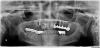

Rinat Опубликовано 28 марта, 2010 Поделиться Опубликовано 28 марта, 2010 (изменено) Здравствуйте!!Мне очень нужен совет, собираюсь провести лечение зубов. Один штифт, правый на снимке, в импланте установленном 2004г сломан. http://i070.radikal.ru/1003/41/29f63142669f.jpg Можно-ли восстановить? Набросайте, пожалуйста, примерный план лечения в моём случае. Очень хочется знать, что предстоит. мой адрес rinatdrh@rambler.ru, тел 89096847951. Есть томограмма в NNTViewer.exe программе, но не знаю как её показать... Изменено 28 марта, 2010 пользователем Rinat Ссылка на комментарий

Doc Опубликовано 28 марта, 2010 Поделиться Опубликовано 28 марта, 2010 Здравствуйте!!Мне очень нужен совет, собираюсь провести лечение зубов. Один штифт, правый на снимке, в импланте установленном 2004г сломан. http://i070.radikal.ru/1003/41/29f63142669f.jpg Можно-ли восстановить? Набросайте, пожалуйста, примерный план лечения в моём случае. Очень хочется знать, что предстоит. мой адрес rinatdrh@rambler.ru, тел 89096847951. Есть томограмма в NNTViewer.exe программе, но не знаю как её показать... Работа непростая. В таких случаях все зависит от возможностей конкретного доктора и Ваших финансовых. Поэтому укажите город, а то не все считают, что Москва единственный город с интернетом, и обращайтесь к москвичам на личную консультацию, ибо вариантов в Вашем случае море и все зависит от желания и возможностей. Ссылка на комментарий